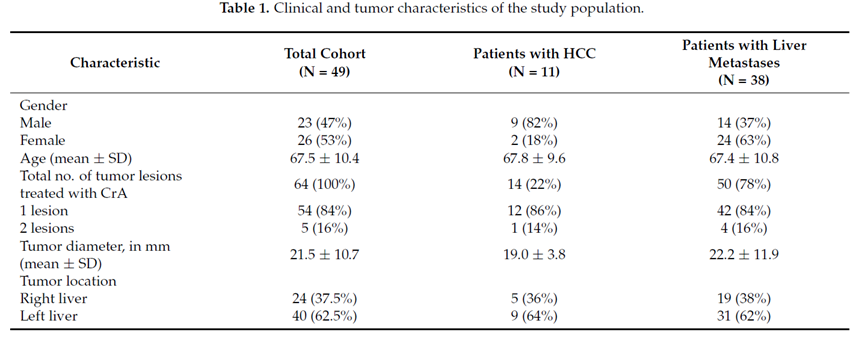

(1)经皮冷冻消融治疗包膜下肝细胞癌(HCC)安全有效。(2)经皮冷冻消融治疗包膜下 HCC 的手术过程简单。(3)包膜下 HCC 患者通过冷冻消融治疗可减轻疼痛,并且仅需局部麻醉。冷冻消融是一种微创治疗方法,可用于治疗原发性和转移性肝癌,对于不适合肝切除或肝移植的患者,冷冻消融在临床上得到广泛的应用。本研究的目的是评估冷冻消融对肝细胞癌和肝转移癌患者的有效性。

回顾性纳入2015 年至 2020 年期间49 名患者,23 名男性和 26 名女性。平均年龄为 67.5 岁(范围 44-85 岁)。平均随访时间为 19.8 个月(范围 1-60 个月)。对 54 个肿瘤病灶进行了 64 次 冷冻消融 手术(50 个转移癌和 14 个 HCC)。平均肿瘤直径为 2.15 cm(范围 0.5-5 cm)。肝脏转移灶来自结直肠 (n = 23)、乳腺 (n = 12)、胰腺 (n = 7)、肺 (n = 3)、甲状腺 (n = 2)、胃 (n = 1)、卵巢 (n = 1) 和宫颈癌 (n = 2)。

技术成功100%,92% 的病灶中观察到肿瘤完全消融。16 名患者 (33%) 出现局部复发。10 名患者 (20%) 因局部复发或肿瘤消融不完全而接受二次冷冻消融术。

7名患者出现轻微并发症,未发现脓肿形成、胆漏、胆汁瘤或血液学变化。冷冻消融可安全、有效治疗毗邻重要脏器的原发性肝脏肿瘤和肝转移瘤患者,有效控制肿瘤局部进展,使患者生存获益。我国作为肝癌大国,对于肝癌的治疗一直给予高度重视。基于专家共识和相关文献研究结果显示,冷冻消融技术具有高效、低成本、创伤小、适应证广、并发症相对较少等优点,可有效延长患者生存期、提高生活质量、降低患者经济负担。因此,冷冻消融技术在肝癌的应用中有着极高的潜力和广泛的发展空间。